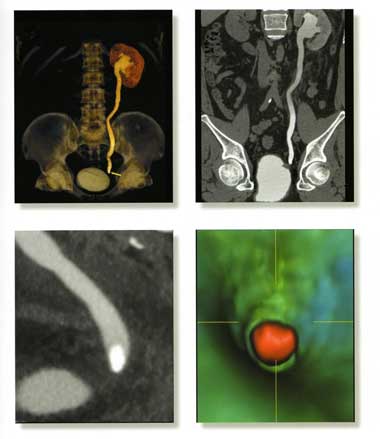

опухоли почек, мочевого пузыря на самых ранних стадиях; мочекаменная болезнь.

Все вышеизложенные методы диагностики проводятся с помощью Мультисрезового спирального компьютерного томографа Toshiba (Asteion Super 4) - 26 декабря 2006 года выпуска, который находится на базе 19-й городской больницы.

Аппарат Toshiba Astieon Super 4: относится к системе 3 поколения с непрерывным оборотом трубки и наиболее подходит для исследования головного мозга и всего тела включая исследования сердечно – сосудистой системы. Многосрезовая технология системы Asteion позволяет получать действительно изотропные объёмные данные. Эта технология позволяет расширить применение КТ и значительно увеличивает диапазон исследований.

Высокое качество изображения и низкая лучевая нагрузка получается за счет эффективного использования дозовой нагрузки.

Томограф фирмы TOSHIBA позволяет не только ставить точный диагноз, но и эффективно лечить пациентов: являясь новатором в технологии КТ, фирма TOSHIBA первая разработала возможность КТ – рентгеноскопии в реальном времени ( КТ – флюороскопия). КТ – это навигация в реальном времени, т.е. специальная флюороскопическая программа дает хирургу возможность проводить пункцию или пункционную биопсию образований, следя за продвижением иглы на экране томографа в реальном времени. Это полностью исключает нежелательное повреждение жизненно важных структур и обеспечивает точность попадания в заданную цель с точностью до 1 мм. Уже сегодня специалисты Центра Эндоскопической нейрохирургии, первыми в Украине, успешно делают бескровные пункционные операции на позвоночнике под контролем компьютерного томотрафа, так называемые пункционная вертебропластика – это когда под контролем томографа в тело поражённого позвонка вводится специальный костный цемент, который через несколько минут застывает. Это эффективный метод предупреждения и лечения патологических переломов позвонков при гормональном остеопорозе и гемангиоме тел позвонков.

Лучевая нагрузка при исследовании на столько низкая, что можно безопасно обследовать даже грудных детей и беременных женщин. Скорость исследования в четыре раза выше, чем на обычном спиральном томографе и составляет считанные секунды. Это особенно важно для тяжелых больных и маленьких детей, которые не могут долгое время лежать неподвижно. Вес пациента не ограничен. Поскольку это исследование абсолютно безопасно, к нему может прибегнуть каждый, кто желает больше знать о своем здоровье. Специалисты томографа, а на нем работают, без преувеличения, лучшие врачи нашей области, подскажут, какое из исследований целесообразнее провести. Но, несомненно, лучший результат достигается тогда, когда пациента направляет лечащий врач, точно формулирующий задачу исследования.